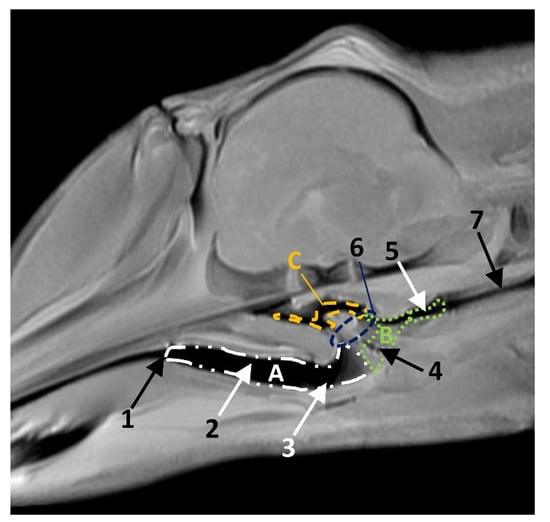

In MRI, we can appreciate, in early fetal stages, a bilateral structure within the laryngopharyngeal cavity, each named as a pharyngeal diverticulum of the auditory tube (PDAT). These are connected through the musculotubaric channel with the middle ear (temporal bone: petrous and tympanic part). In a young Delphinus delphis fetus (dde3), it appears in sagittal sections as a hyper/hypointense area seen caudal and rostrally, respectively (Figure 26A,B), and also in coronal sections (Figure 26C,D).

In older Delphinus delphis fetuses (dde5, dde8, dde11) this double space at both sides of the laryngopharynx is more evident and shows the same intensity, but now we can distinguish the vascular area (hyperintense) and the air-filled area (hypointense) (Figure 27, Figure 28, Figure 29, Figure 30 and Figure 31).

In more advanced fetal development, it is possible to observe air (hypointense) and vascular (moderate hyperintense) areas, and even the auditory tube (slightly hypointense) (Figure 30).

PDAT were clearly seen in sagittal and coronal sections in a Grampus griseus fetus (grgr1). The T2 sequences are clearer than T1 because they differentiate two areas: slightly hypointense (vascular) and hyperintense (air) (Figure 31).

Figure 26. Images of the pharyngeal cavity. MR sagittal and coronal images are oriented so that the rostral is to the right. (A) T1 SE sagittal, (B) T2 FrFSE sagittal, (C) T1 SE coronal and (D) T2 FrFSE coronal planes. 4 months, dde3. 1, Inner and middle ear; 2, Pharyngeal diverticulum of the auditory tube.

Animals 11 01507 g026

Figure 27. Images of the pharyngeal cavity. MR coronal and sagittal images are oriented so that the rostral is to the right. (A,B) T2 FrFSE sagittal, (C) T1 SE and (D) T2 FrFSE coronal planes. 5.5 months, dde5. 1, Inner ear; 2, Pharyngeal diverticulum of the auditory tube: moderate hyperintense area (vascular); 3, Pharyngeal diverticulum of the auditory tube: hypointense area (air).

Animals 11 01507 g027